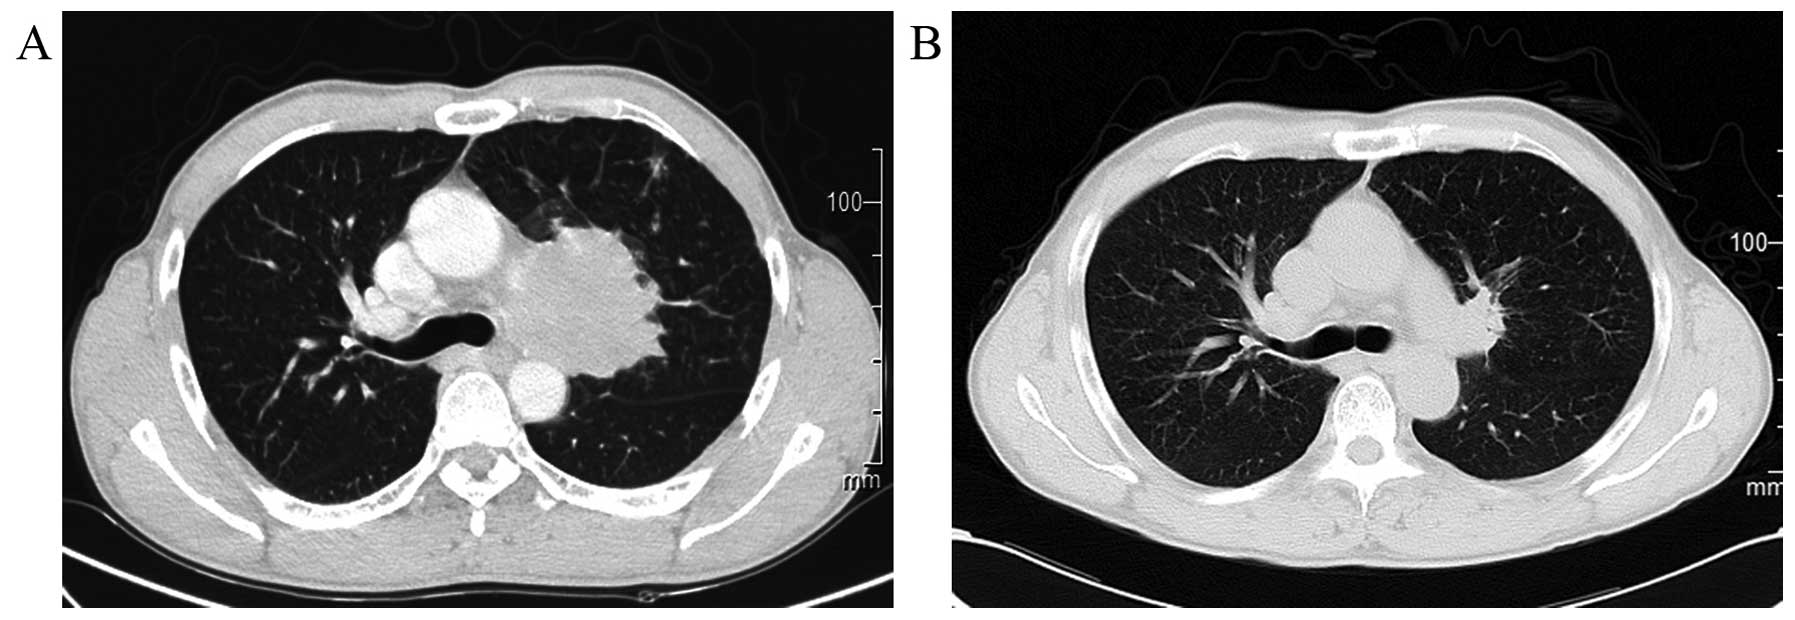

Small-cell lung cancer (SCLC) presenting with syncope as the initial symptom is rare in adults. This onset of tumour-induced syncope cannot be screened or differentiated by coronary angiography, magnetic resonance angiography of the neck or 24-hour dynamic electrocardiogram. We herein describe the case of a 61-year-old man who presented with recurrent syncope that resolved after the first course of chemotherapy (carboplatin plus etoposide) for SCLC. A mass measuring 57x53 mm was identified in the left hilum, and a diagnosis of limited-disease SCLC (T4N2M0, IIIB) was made. Considering the rapid and complete remission after the treatment of the primary lesion, we hypothesised that the syncope was neurogenic and associated with cancer. Thus, 8 similar cases retrieved from PubMed were reviewed and, for the first time, the mechanism underlying the syncope was identified, which may involve tumour location, neurobiology and other inducing factors. Thus, for the treatment of such SCLC patients, standard chemotherapy is crucial for preventing syncopal attacks.

Figure 1